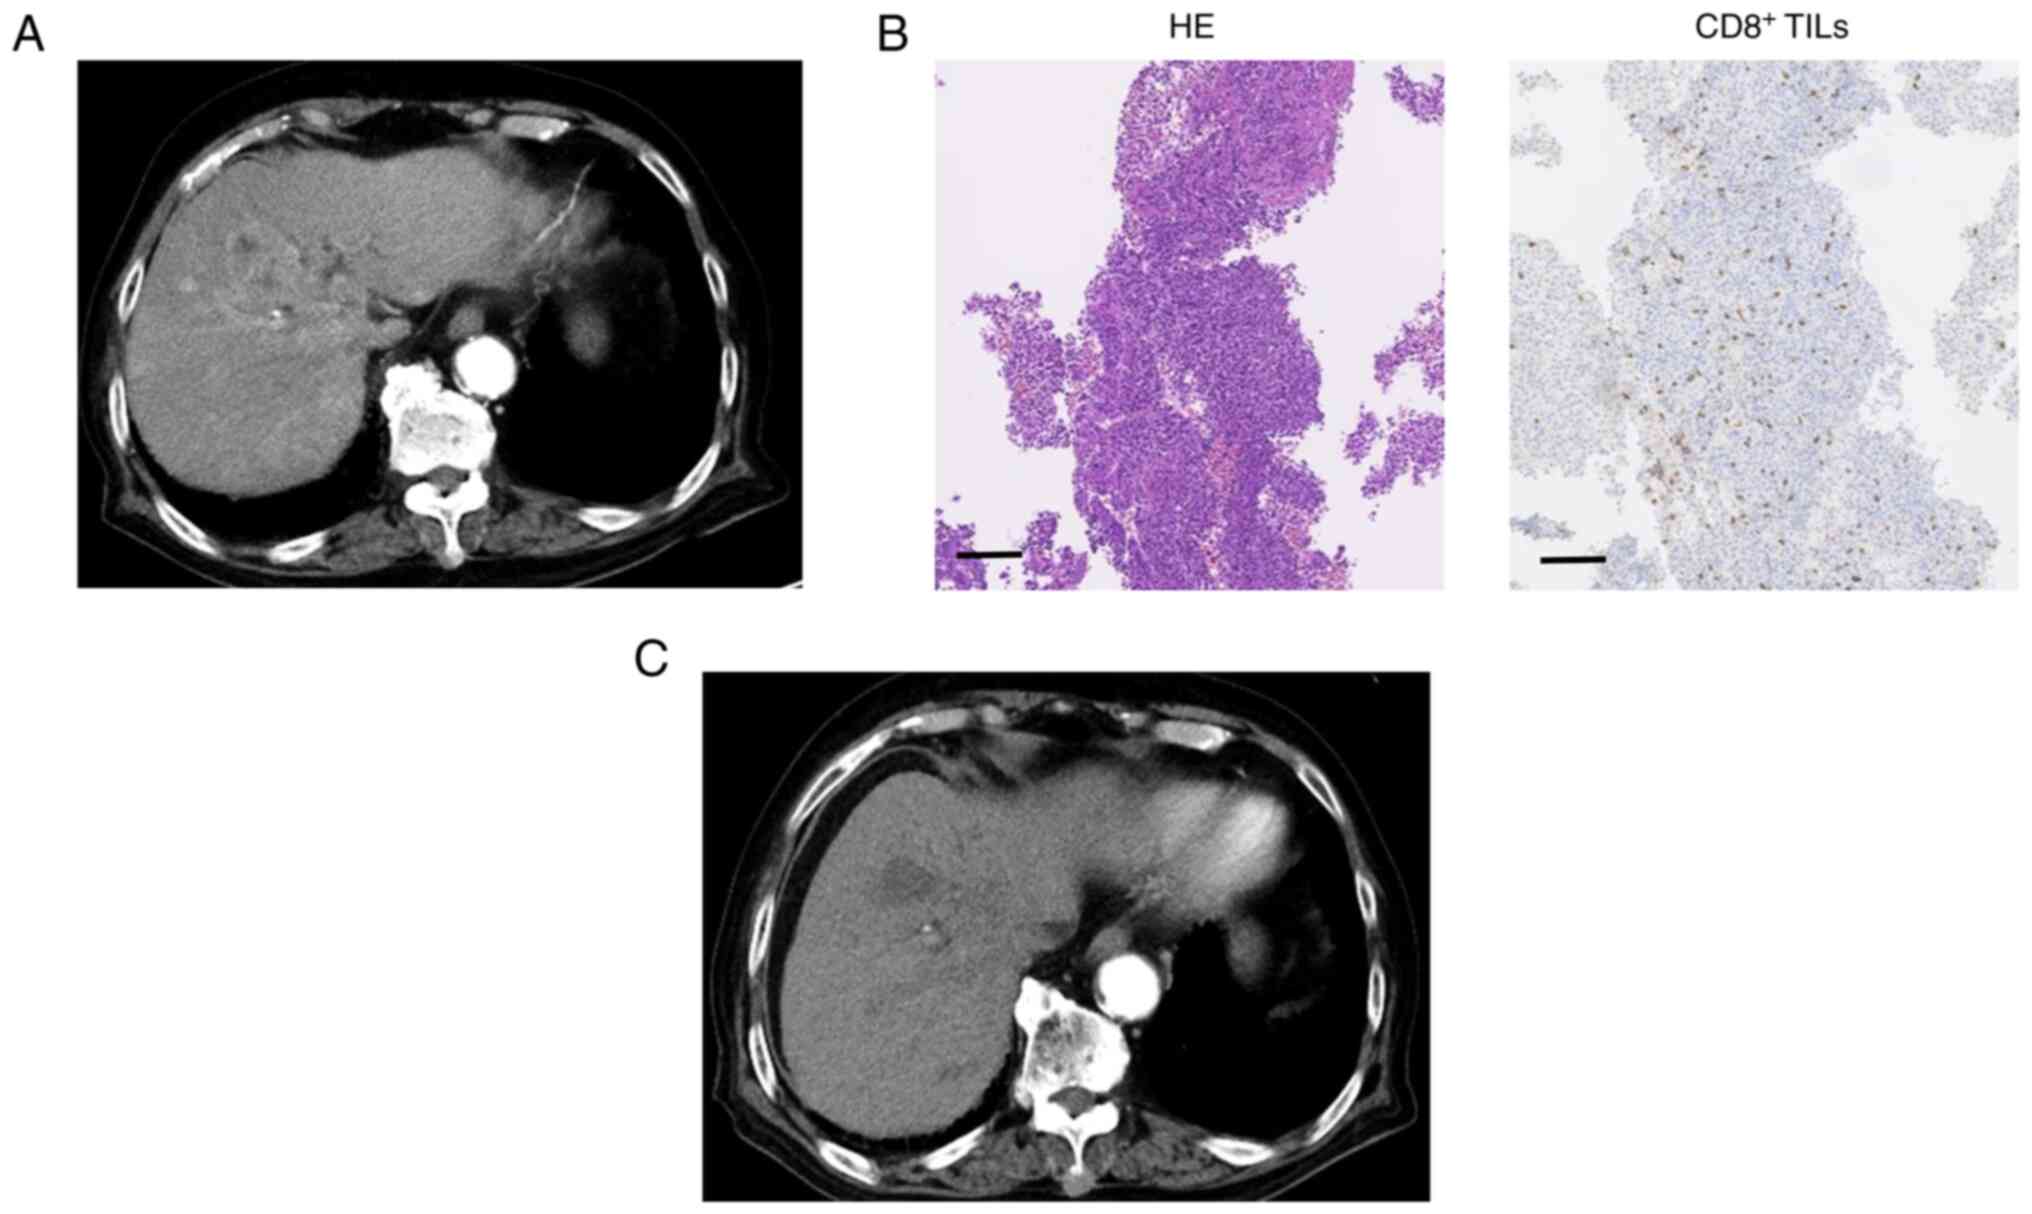

CD8 +TIL levels were assessed by IHC prior to atezolizumab plus bevacizumab treatment. Typical cases are shown in Figs. 1 and 2. Case 1 was an 88-year-old man with unresectable multiple HCC related to hepatitis C virus infection (Fig. 1). IHC staining of this poorly differentiated HCC indicated high levels of CD8+ TILs. Following administration of atezolizumab plus bevacizumab, liver CT images showed a reduction in the size and enhancement of the arterial stage of the tumor, indicating a PR. The patient's serum AFP level was 1,779.7 ng/ml before treatment, which decreased to 52.5 ng/ml after four cycles. Case 2 was a 78-year-old man with hepatitis C virus-related advanced HCC (Fig. 2). The specimen was diagnosed as poorly differentiated HCC, and IHC staining showed low CD8+ TIL levels. Post-treatment CT images showed an increase in tumor size, indicating disease progression. The patient's serum AFP level was 3,337.6 ng/ml before treatment, which increased to 11,028.0 ng/ml after four cycles.

Figure 1.

Typical Case 1, high-level CD8+ TILs. (A) CT image of the early arterial phase prior to treatment. (B) HE-staining of liver specimens (magnification, ×100; scale bar, 100 µm). Immunohistochemistry staining for CD8+ T cells was conducted in liver specimens (magnification, ×100; scale bar, 100 µm). (C) CT image of the early arterial phase to evaluate treatment efficacy. TILs, tumor-infiltrating lymphocytes; CT, computed tomography; HE, Hematoxylin and eosin.